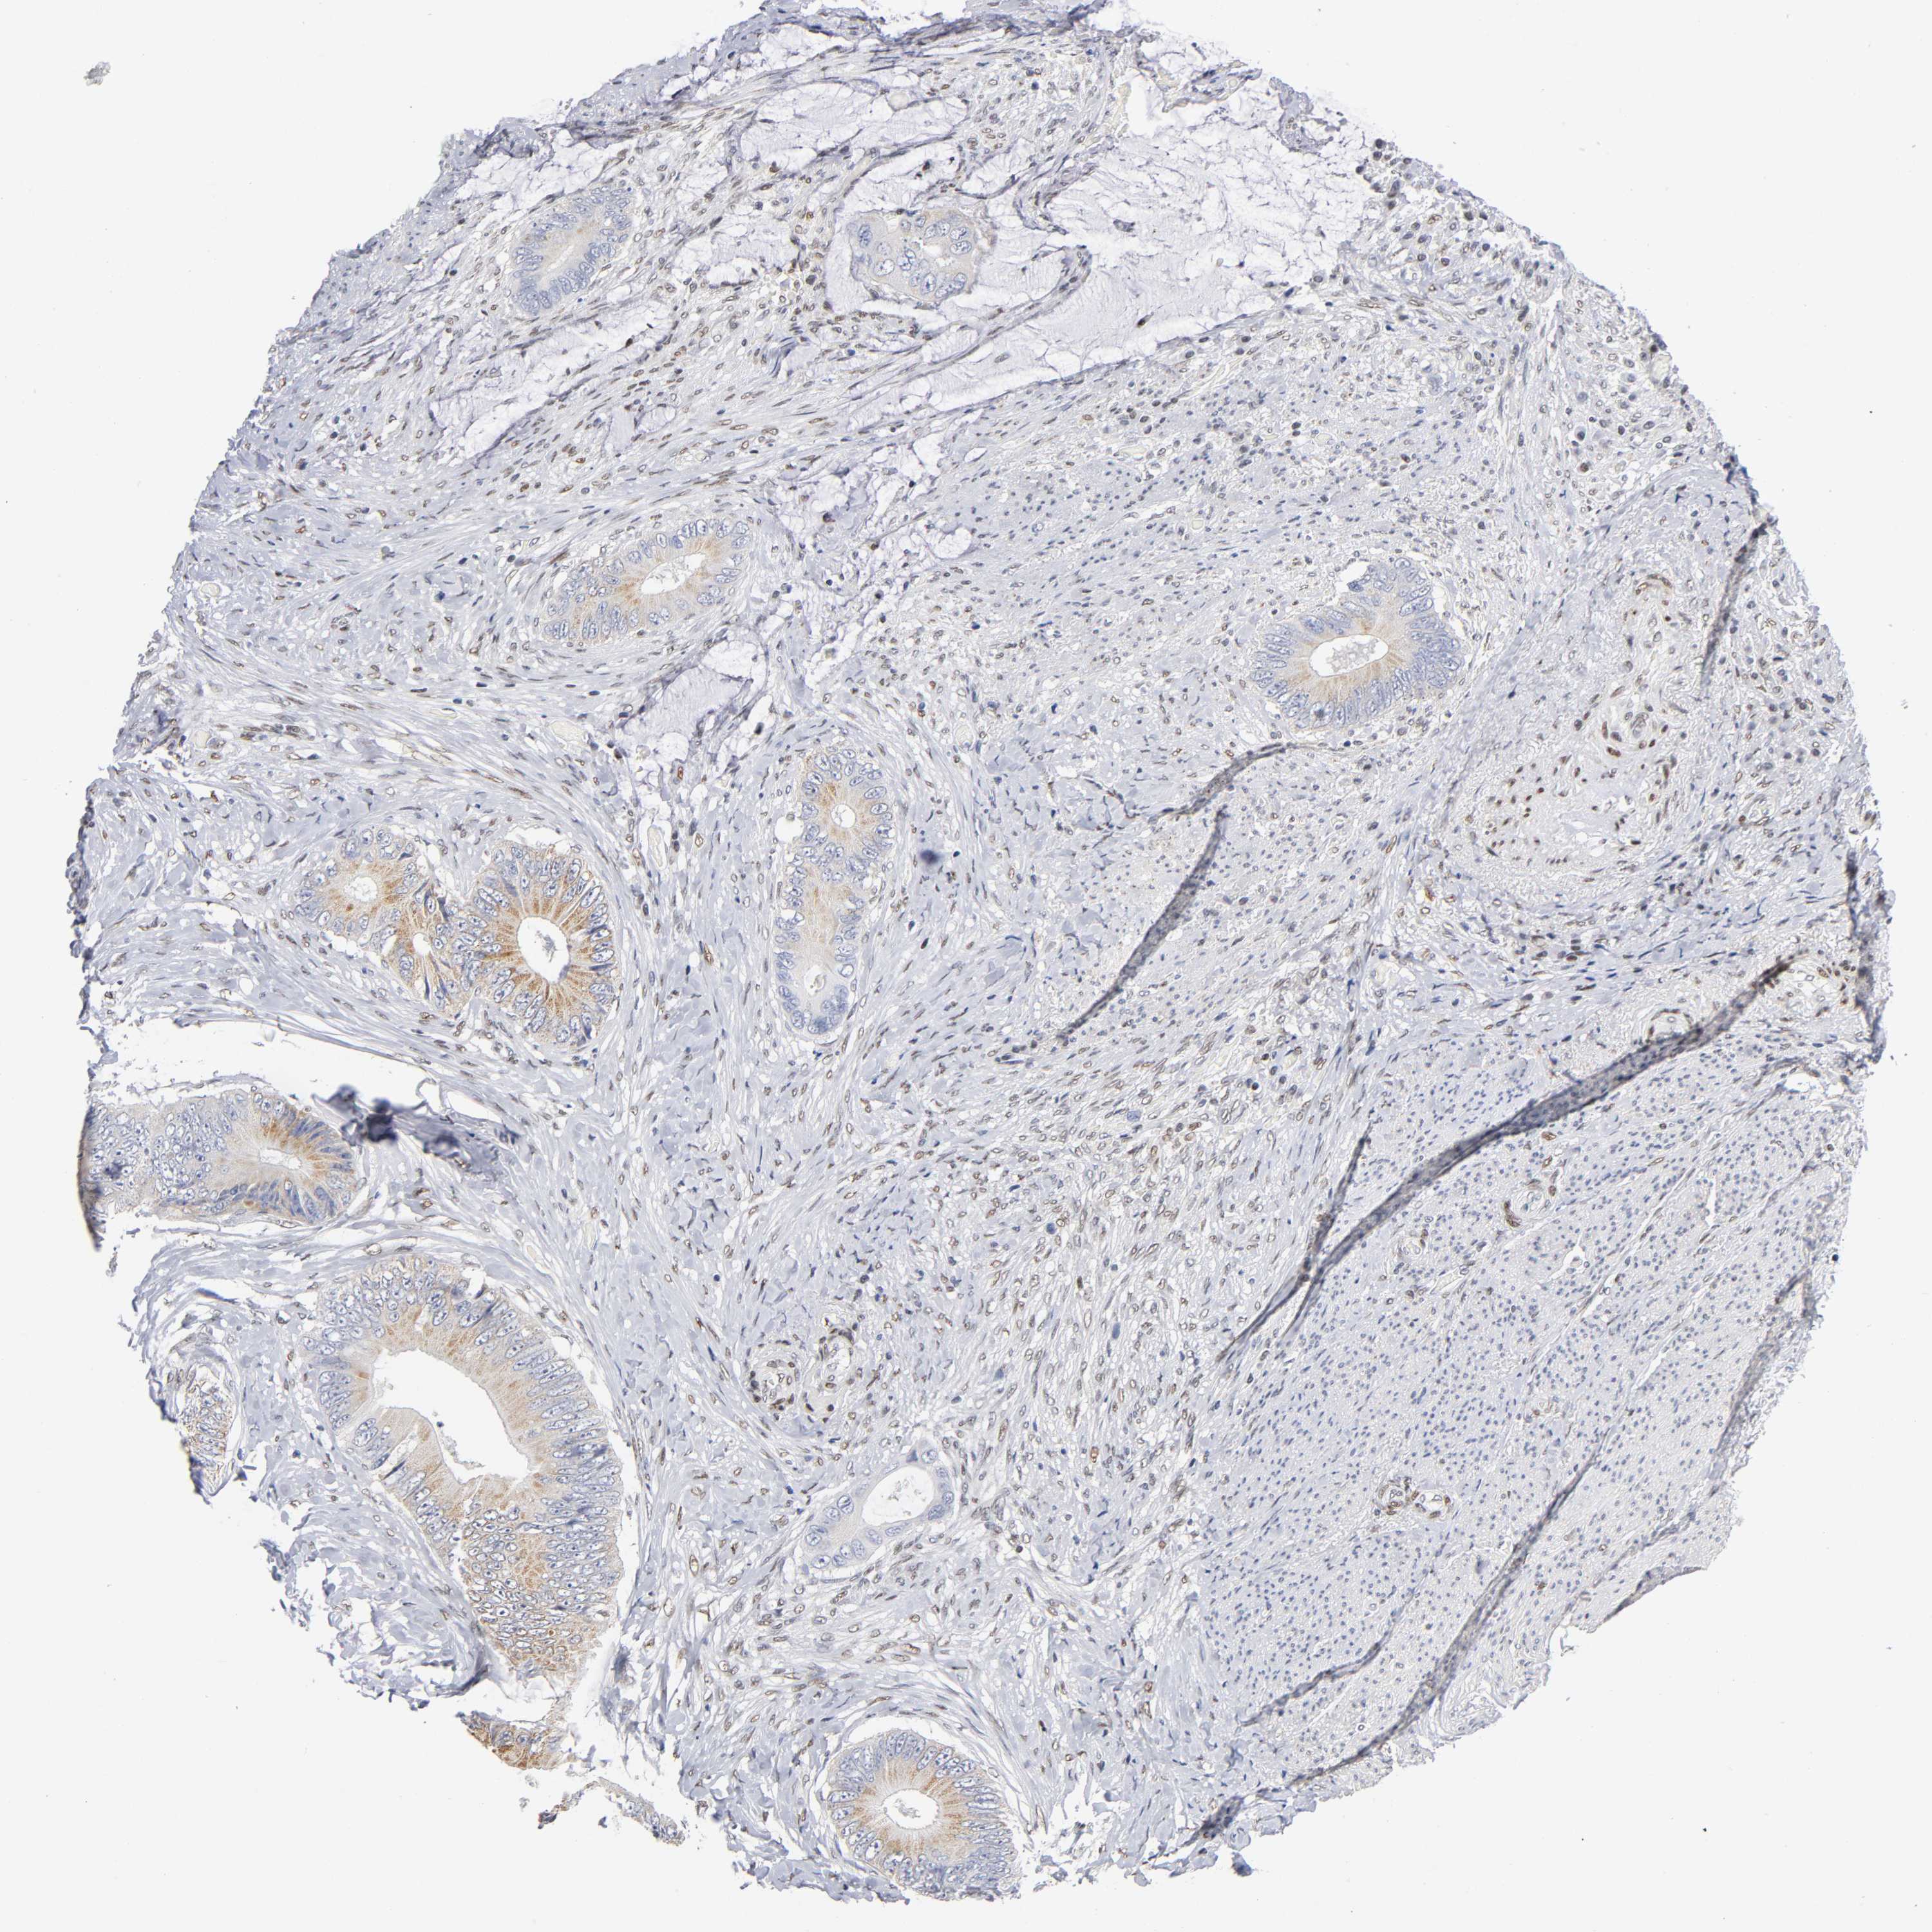

CANCER COLORECTAL CANCER Show tissue menu

Colorectal cancer

Human cancer

Colon adenocarcinoma